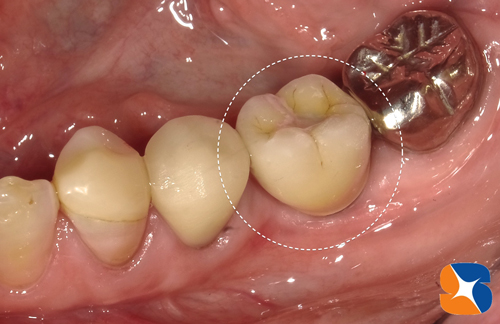

〈手術から3ヶ月後〉

3ヶ月過ぎから仮歯を装着します。1ヶ月間使っていた後、最終の型取りに入ります。

施術から4ヶ月後、無事にセラミックで仕上げたインプラントが完成いたしました。